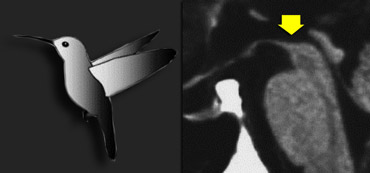

PSP with midbrain atrophy PSP with midbrain atrophy

Progressive supranuclear palsy (PSP)

PSP is also one of the atypical parkinsonian syndromes.

In PSP there is pronounced atrophy of the midbrain (mesencephalon), which accounts for the typical upward gaze paralysis.

PSP: 'humming bird sign' due to midbrain atrophy PSP: 'humming bird sign' due to midbrain atrophy

Normally the upper border of the midbrain is convex.

The atrophy of the midbrain in PSP results in a concave upper border of the midbrain with the typical 'humming bird sign' (figure).